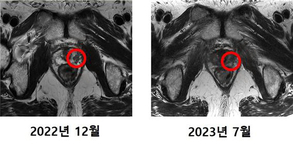

연세암병원, 국내 첫 중입자치료 환자의 암 조직 제거 확인

- 2023-09-19 11:17

- 이형규 기자